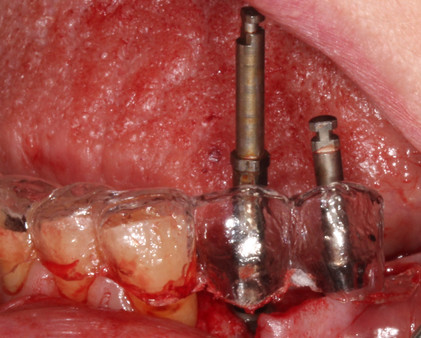

Surgical Phase - Stage 1- Implant placement with surgical guide - Lower premolars.

The surgical guide used to guide during surgery, short implants were used. Astra tech 3.5 mm implants of 6mm and 8 mm were used due to the close proximity to the nerves.